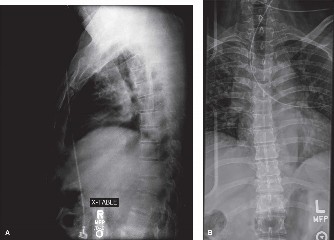

Appreciate the relative outcomes of different surgical approaches to this problem? CASE 15 A 62-year-old woman underwent a routine single-level L4–5 laminectomy and posterior instrumented fusion for spinal stenosis with degenerative spondylolisthesis. She reports substantial symptomatic improvement for 10 years but now presents with recurrent low back pain and increasing leg pain when walking distances. Figure 1–22 shows a lateral plain radiograph taken 1 year after surgery. Figure 1–23 shows the same view at 10-year follow-up.

Figure 1–22

Figure 1–23

The correct answer is (C). The two radiographs depict interval development of an

L3–4 spondylolisthesis immediately proximal to an L4–5 spinal fusion. In the setting of a patient with recurrent back pain and claudication symptoms several years after initially successful lumbar laminectomy and fusion surgery, the radiographic findings strongly suggest development of adjacent segment degeneration and imply symptomatic spinal stenosis at the L3–4 level (though not appreciable on plain films). L4–5 nonunion can present in delayed fashion several years after surgery but is more often associated with mechanical back pain as opposed to recurrent claudication. In addition, a plain lateral radiograph would not be sufficient to make this determination. L3 spondylolysis can result from weakness of the pars interarticularis following laminectomy. However, the L3 pars is clearly seen and appears to be intact. This would also not be associated with claudicant-type symptoms. Finally, flatback syndrome can result in back pain and bilateral thigh cramping secondary to postoperative sagittal imbalance but does not cause claudication. This patient’s lordosis appears to be preserved.

The correct answer is (C). Overall, the incidence of adjacent segment disease appears to be approximately 25% to 30% within 10 years of the index surgery. The relative risk based on specific spinal level appears to vary directly with relative segmental motion and is therefore greatest at the L4–5 level. Of all surgery-related risk factors studied to date, one of the most consistently demonstrated risk factors for increased adjacent segment stress and degeneration appears to be sagittal plane imbalance, specifically kyphotic malalignment.